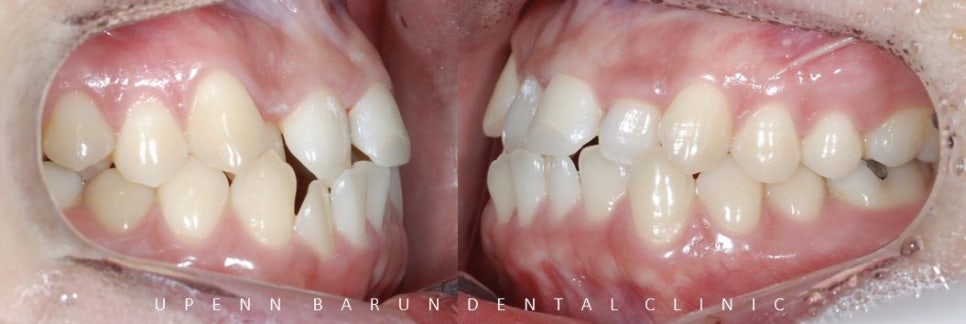

환자분께서는 앞니가 거꾸로 물리는 반대교합이 있고

앞니가 치아끼리 맞물려

구조적으로 앞니가 깨지기 쉬운 상태셨습니다 T^T

치아가 모두 고르게 펴질수 있는 공간이 협소해서

발치교정도 생각해 볼수 있었으나,

환자의 안모 등 여러가지 사안들을 고려해서

비발치 교정에 적합한 '데이몬교정장치' 로 잠실치아교정을 진행했습니다.